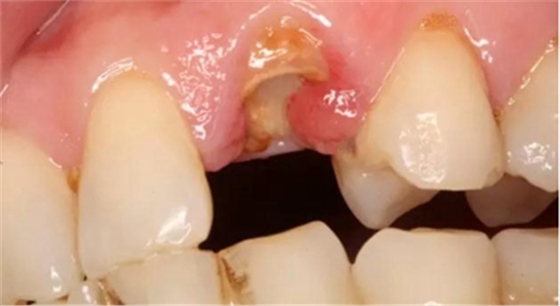

下面為一例纖維樁全冠修復(fù)后,纖維樁斷裂的病例,同樣實行了冠延長手術(shù)。

患者女性,55歲,3年前B3纖維樁+鑄瓷全冠修復(fù),一周前牙冠折斷,就診后,發(fā)現(xiàn)纖維樁根管口處折斷,周圍牙齦增生,建議患者行冠延長手術(shù)。首先去除斷端的纖維樁。拍片示牙根長度充足。于是開始冠延長手術(shù)。

因為是前牙,故該患者將來修復(fù)體邊緣必須為齦下,所以3個月后再行修復(fù)。以下為手術(shù)前照片。

以下為術(shù)中照片。

內(nèi)斜切口,頸圈組織,改良垂直褥式縫合。